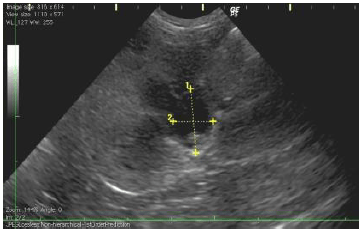

![]() |

|

左側が手術前、右側が手術後のエコー画像です。

手術前は尿が腎臓内に溜まってしまい水腎症の状態ですが(黄色矢印の黒い部分が流れないで溜まっている尿です)、術後正常な腎臓の構造に戻っている事が確認できました。 手術後は尿も流れるようになり、体調も回復し元気に退院できました。

上側が手術前、下側が手術後のエコー画像です。

手術前は尿が腎臓内に溜まってしまい水腎症の状態ですが(黄色矢印の黒い部分が流れないで溜まっている尿です)、術後正常な腎臓の構造に戻っている事が確認できました。 手術後は尿も流れるようになり、体調も回復し元気に退院できました。 |